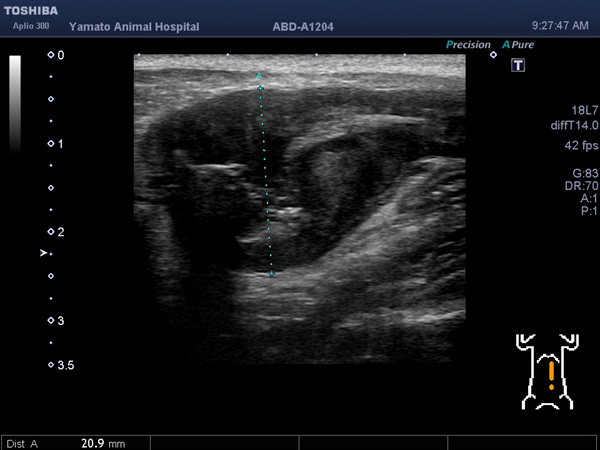

猫ちゃんが嘔吐と食欲不振の症状で来院されました。超音波画像から腫瘍による腸閉塞が疑われたため、開腹手術を行いました。病理組織検査の結果は「リンパ腫(高グレード、貫壁性)」でした。その後、抗がん剤による治療となりました。